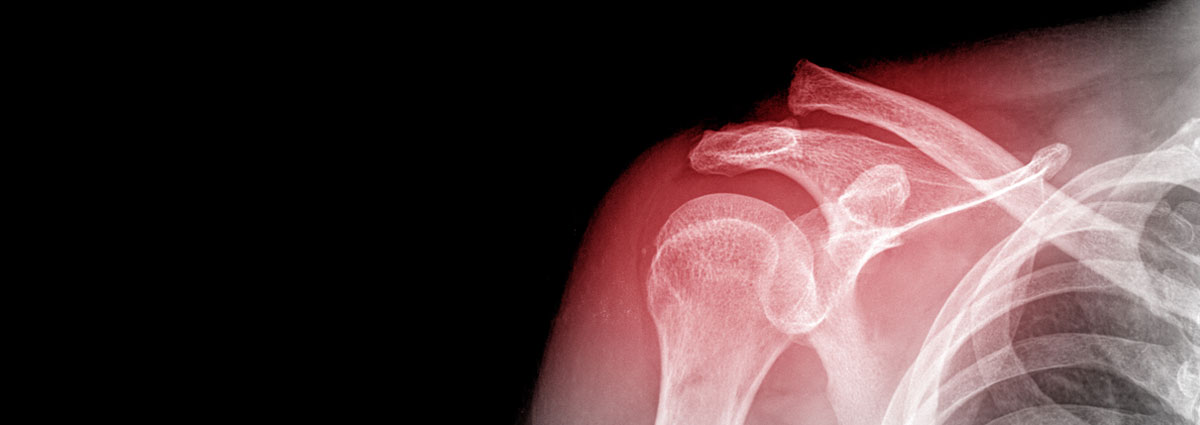

L'espatlla és l'articulació que connecta el tronc amb el braç i està format per tres ossos: escàpula o omòplat, clavícula i húmer. Envoltat per cartílag que permet un moviment suau i indolor, l'espatlla es divideix en dues cavitats articulars, l'espai subacromial (on es troben els tendons del maniguet rotatori), la funció del qual és estabilitzar l'articulació de l'espatlla quan s'eleva el braç i realitzar la flexió i rotació externa del braç) i l'articulació glenohumeral (on es troben els lligaments que actuen de reforç i que donen estabilitat a l'espatlla per evitar la luxació articular).

- Fracturas

Las fracturas son lesiones producidas por un traumatismo de mayor intensidad que origina una rotura del hueso. Las fracturas en la articulación del hombro se pueden producir en cualquiera de los 3 huesos que lo forman:

- Fractura de la clavícula: suelen producirse por una caída sobre el hombro, el cual transmite la fuerza deformante hacia la clavícula produciendo su fractura.

- Fractura de la escápula u omóplato: son poco frecuentes y se suelen producir en traumatismos de gran energía en los que se ven afectados hombros, tórax y columna.

- Fractura de la cabeza humeral: también implican un traumatismo de gran energía. Esta lesión se da con más frecuencia en gente de edad avanzada debido a la disminución en la densidad ósea.

El daño y el tipo de fractura marcarán el tratamiento a seguir (reposo, medicación, etc). Si la fractura es grave, será necesaria una intervención quirúrgica para colocar de nuevo los huesos en su posición normal.